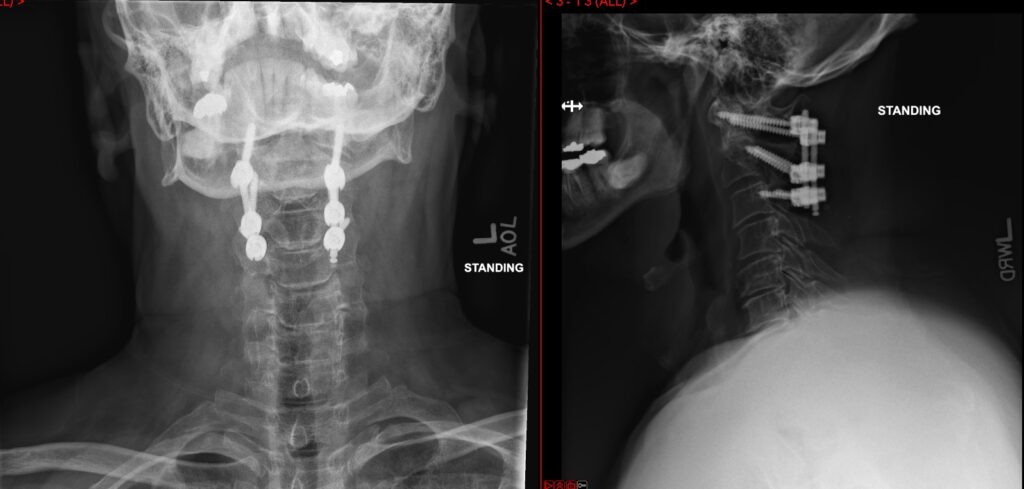

C1-2 fusion